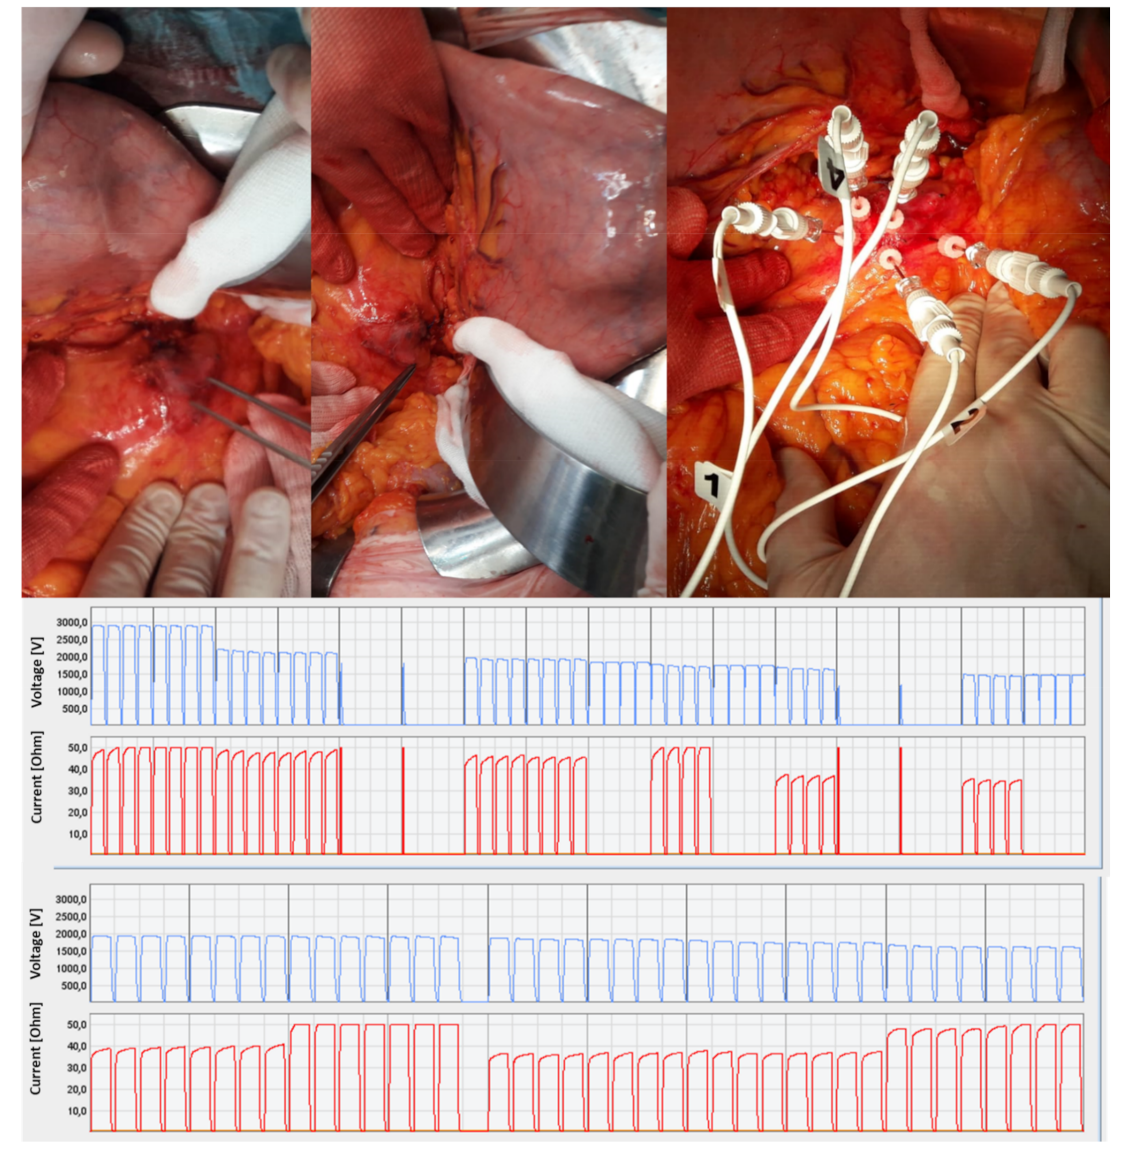

2.2.Treatment Protocol

3.2. Secondary Endpoints Assessment (Feasibility and Safety)